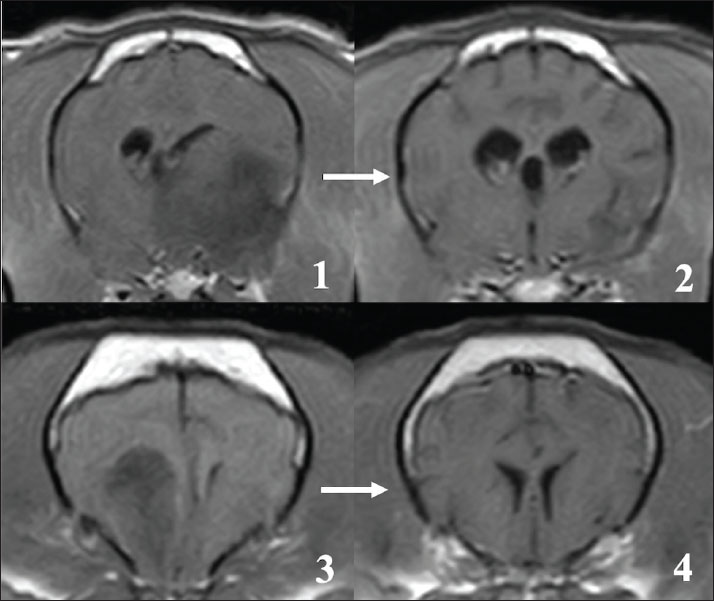

Magnetic resonance imaging of four early deaths (B1–B4)

In this study, 4 cases could not complete the radiation therapy. Among these, 1 case died before starting treatment (B1), and 3 cases died during radiation therapy (B2–B4). Although the cause of death was not clearly identified because an autopsy could not be done, 2 cases that died after the first fraction showed cerebellar herniation on MRI at the first visit, possibly due to large tumor size (Fig. 5,1).

On MRI at the first admission in these 4 cases, leptomeningeal enhancement, as seen in cases A1–A4, was also observed, although the changes were less prominent (Fig. 5, 1-3). In 1 case (B2), multiple mass lesions were observed. In addition to the primary lesion, another presumed tumor tissue was observed, which appeared to be contiguous with the meninges on MRI, showing clear enhancement (Fig.5, 4-7).

Fig. 5. MRI at the first visit of the cases that died early after visiting our hospital (cases B2–B4, T1: T1-weighted image, T2: T2-weighted image, and T1C: T1-weighted image with contrast medium). Upper lane 1: Cerebellar herniation was observed on the sagittal plane (yellow arrow) in case B3, possibly due to the large tumor size. Upper lanes 2 and 3: At the time of the first visit, enhancement was already observed in the leptomeningeal region around the brainstem (B4, yellow arrow), but was less prominent compared with cases A1–A4. Lower lane 4–7: In case B2, the tumor tissue considered to be the primary lesion showed heterogeneous enhancement (4, 5). Furthermore, another mass contiguous with the meninges was observed. This mass shows a clear enhancement (6, 7, yellow arrow).

Furthermore, in the other 4 cases that died early in their treatment course (B1–B4), the characteristics of CSF drop metastasis might have been present on MRI at the first visit, although less prominently. In these cases, it is possible that CSF drop metastases had already occurred at the time of the first visit, and they might have resulted in more severe clinical symptoms compared with those cases with completed radiotherapy. In case B2, a tumor lesion other than the primary tumor that was contiguous with the meninges was observed. These meningeal mass lesions are similar to those in the MR images showing CSF drop metastasis in a previous report (Bentley et al., 2021). The effect of CSF drop metastasis on survival time in FB with oligodendroglioma could not be accurately determined because the definitive cause of death in most cases could not be identified in this study. However, given that the MST of the FBs in this study did not sufficiently prolong, CSF drop metastasis may shorten the survival of FB glial tumor cases.